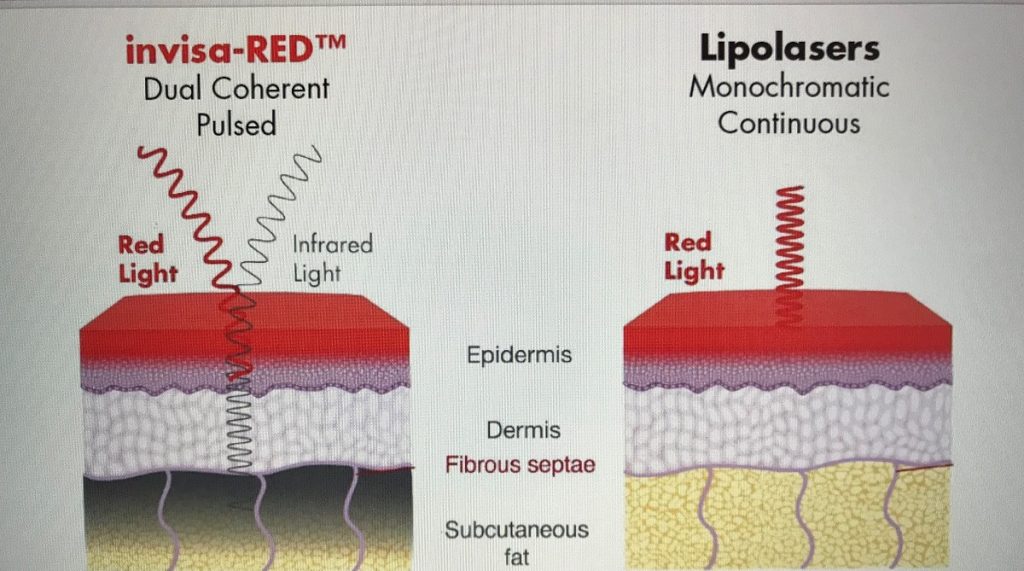

– InvisaRed Laser to reduce fat (FDA approved), approximately 1/2 lb. of fat per session.